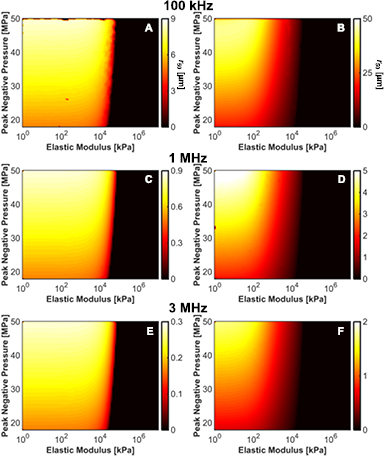

3.7. Red blood cell viability surrounding histotripsy-induced cavitation

The viability of red blood cells is shown as a function of distance from the bubble wall for microtripsy excitations in figure 9, and for a single-cycle shock-scattering histotripsy excitation in figure 10. Strains were computed analytically at the maximum bubble diameter for Kelvin–Voight elasticity. The red blood cell viability increased rapidly from 0% at the bubble wall to 100% within 50 µm for all insonation conditions. The red blood cell viability increased sigmoidally as a function of distance away from the bubble wall, and was fit to a function of the form:

where d is the distance from the center of the bubble, and d0 and ds are fitting parameters. The parameter d0 was used to express the distance from the bubble wall over which the predicted red blood cell viability decreased by 50%:

Standard image High-resolution imageThe frequency, pressure, and elasticity dependence of r50 had a similar form to that for the maximum bubble size, as indicated in figure 11. For a medium with elastic modulus greater than 20 MPa, r50 approached 0 µm as bubble expansion was completely suppressed. For fixed medium elasticity and insonation conditions (peak negative pressure and fundamental frequency), r50 was greater for microtripsy pulses than shock scattering histotripsy pulses (table 3). Thus, the distance over which bubble expansion effects red blood cell viability is greater for microtripsy compared to shock scattering histotripsy. For fundamental frequencies greater than 1 MHz, changes in red blood cell viability did not extend beyond 5 µm, roughly the size of a red blood cell (Lewis 1996).

Table 3. The maximum and mean values for r50 as a function of frequency and insonation type. Here, the average value is tabulated over the peak negative pressures and elastic moduli considered in the study.

| Histotripsy type | Max r50 (µm) | Mean r50 (µm) |

|---|---|---|

| Microtripsy | ||

| 100 kHz | 44.3 | 11.15 |

| 1 MHz | 5.22 | 1.70 |

| 3 MHz | 1.75 | 0.55 |

| Shock scattering | ||

| 100 kHz | 8.60 | 4.37 |

| 1 MHz | 0.86 | 0.45 |

| 3 MHz | 0.29 | 0.15 |

Figure 11. Distance from bubble wall to 50% reduction in red blood cell viability in micrometers, r50, induced by bubble expansion as a function of elastic modulus and peak negative pressure for shock-scattering histotripsy (left column) and microtripsy (right column) excitations. (A) and (B) 100 kHz fundamental frequency. (C) and (D) 1 MHz fundamental frequency. (E) and (F) 3 MHz fundamental frequency.

Download figure:

Red blood cell viability surrounding histotripsy cavitation activity was modeled based on measurements of impulsive stretching of erythrocytes (Li et al 2013). Strain fields surrounding the bubble were rapidly attenuated within 50 µm from the bubble wall, consistent with previous calculations of histotripsy-induced cavitation (Mancia et al 2017). Only red blood cells within a few micrometers from the bubble wall experienced lethal strain (table 3), and the erythrocyte viability increased sigmoidally with distance away from the bubble. On a macroscopic level, the limited distance over which red blood cell viability is reduced observed in this study is consistent with the sharp boundaries observed in histotripsy lesions (Parsons et al 2006, Kieran et al 2007, Vlaisavljevich et al 2013a, Darnell et al 2015). In vitro studies have demonstrated histotripsy-induced breast cancer cell bisection occur only within a few micrometers to a nucleated bubble (Vlaisavljevich et al 2016). Under the similar insonation conditions, the calculations in this study indicate changes in red blood cell viability would be restricted within 1 µm of the bubble (figures 11(C) and (E)).

Tissue elasticity was observed to influence the degree of bubble expansion, and the subsequent strain surrounding the bubble. Erythrocyte viability for a given histotripsy exposure will be restricted to the bubble wall in highly elastic tissue, reducing the volume of red blood cell lysis. This has implications for the age of histotripsy-treated thrombus. Retraction of the thrombus over time changes its elasticity (Xie et al 2005) and composition (Sutton et al 2013). Zhang et al (2016) noted a change in in elastic modulus from 2.31 kPa for unretracted clots to 11.12 kPa for retracted clots, with a significant reduction in the efficacy of 1 MHz microtripsy pulses. Interestingly, the calculations here suggest a 1.1% decrease in bubble expansion and 3.5% reduction in red blood cell lysis over the same range of elastic moduli. The change in thrombus structure may alter the acousto-mechanical properties, increasing the attenuation of the histotripsy field (Nahirnyak et al 2006). Alternatively, anisotropies in fibrin-rich clot may not be properly modeled by the normal strains computed in this study (Weiss et al 2013). Up to 43% of thrombi are multifaceted, with both acute and chronic portions (Mewissen et al 1999, Gagne et al 2015). To ensure sufficient mechanical action throughout the thrombus, histotripsy image guidance should thus focus on not only qualifying the presence of cavitation, but also spatially quantifying the degree of cavitation activity (Macoskey et al 2017, Bader et al 2018).

In media stiffer than 20 MPa, calculations indicate the strain on erythrocytes is insufficient to induce lysis for the histotripsy insonation parameters considered (figure 11). In softer media, the extent of damage beyond the bubble volume was found to depend on the insonation type. Microtripsy-nucleated bubbles induce larger strains at greater distances from the bubble compared to shock scattering cavitation for a given set of insonation parameters. Depending on the necessity for precision relative to the observed spatial location of the bubble cloud, the choice of insonation scheme should be considered.